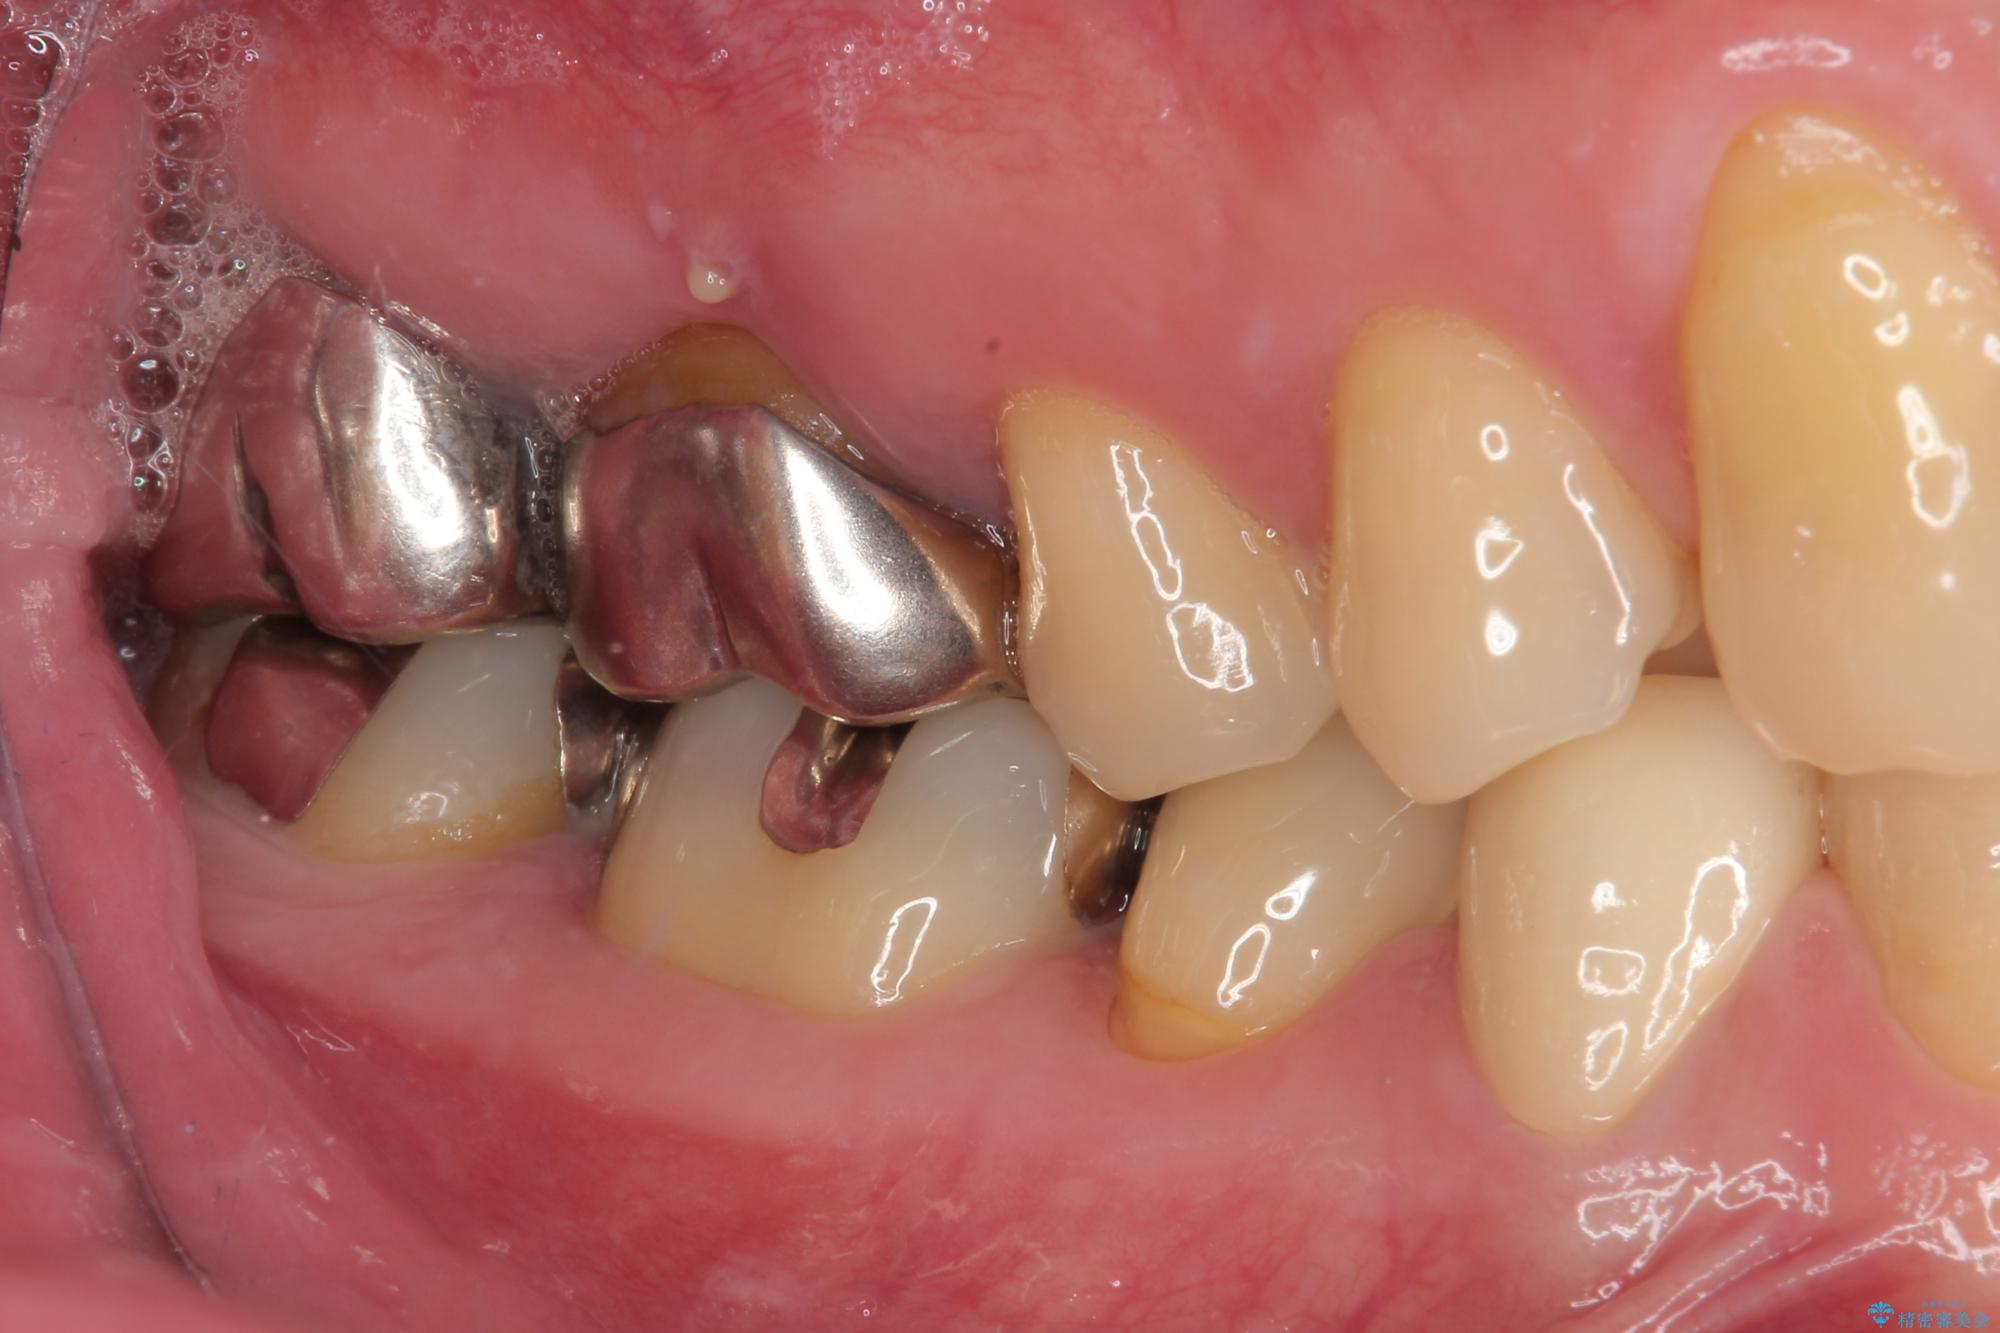

拡大鏡視野下で虫歯を除去しオールセラミッククラウンに適した形に整えました。

歯と歯茎の間に圧排糸と言われる糸を入れてシリコーン印象材にて型どりをしました。